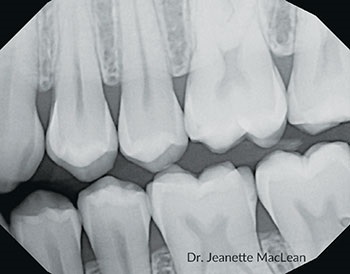

Fig. 5: A 19-year-old male with incipient proximal caries lesion on the distal of the mandibular left first permanent molar.

Fig. 7: A six-month follow-up bitewing shows the distal lesion on the mandibular left first permanent molar has not cavitated.